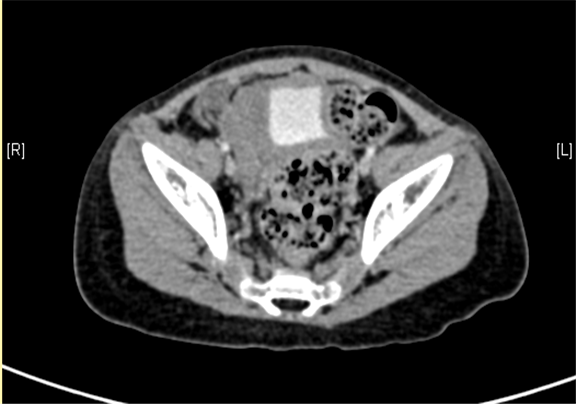

下腹部增强CT示右下腹腔内巨大软组织块影并右肾、输尿管积水。

术前CT检查:

平衡期